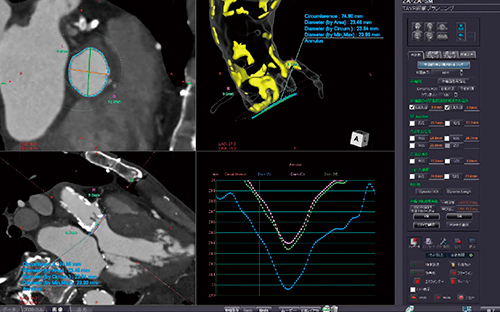

大腿動脈から弁を留置する経大腿アプローチでは,血管の蛇行や狭窄,石灰化の評価に加え,シースサイズを選択してシミュレーションを行うことが可能であり,計測ポイントも自動で計測する(図5)。TAVRに関するガイドラインやデバイスメーカーのプロクタリングで推奨されている術前計測に対応するレポート出力機能も,今回新たに搭載した(図6)。心尖部から弁を挿入する経心尖アプローチに対しては,心筋の厚み,大動脈弁へのアプローチ角度など,TAVRの術前に必要な情報を計測できる。また,TAVRにおいて,最も重要な術前シミュレーションに弁輪面の解析がある。TAVR術前プランニングでは,大動脈の自動抽出および弁輪面の自動計測を可能としており,従来の弁輪面計測と異なり,1つのフェーズをトレースするだけで1心拍分のすべてのフェーズを追従した自動計測が可能だ。この機能は,“PhyZiodynamics”テクノロジーにより実現されたZiostation2だけの機能である。また,サーフェスレンダリング表示にも対応し,より正確なシミュレーションを可能としている(図7)。

図7 弁輪面の自動計測とサーフェスレンダリング表示